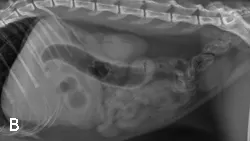

A) Right radiograph, B) Left radiograph, and C) Ventrodorsal radiograph

Radiographic Findings: The stomach (St) and duodenum (D) are severely distended with fluid and gas, suggesting intestinal obstruction or possibly pancreatitis with secondary ileus.

Comments: We often perform left and right lateral radiographic views of the abdomen in cases of suspected GI foreign bodies and obstructions since the fluid and gas disperse into different portions of the GI tract. For example, any gas in the stomach rises to the pylorus (P) in left lateral recumbency and may outline a foreign body anchored to this region; this is particularly useful in suspected linear foreign bodies, which typically anchor to the tongue or pylorus and subsequently plicate varying degrees of small intestine.